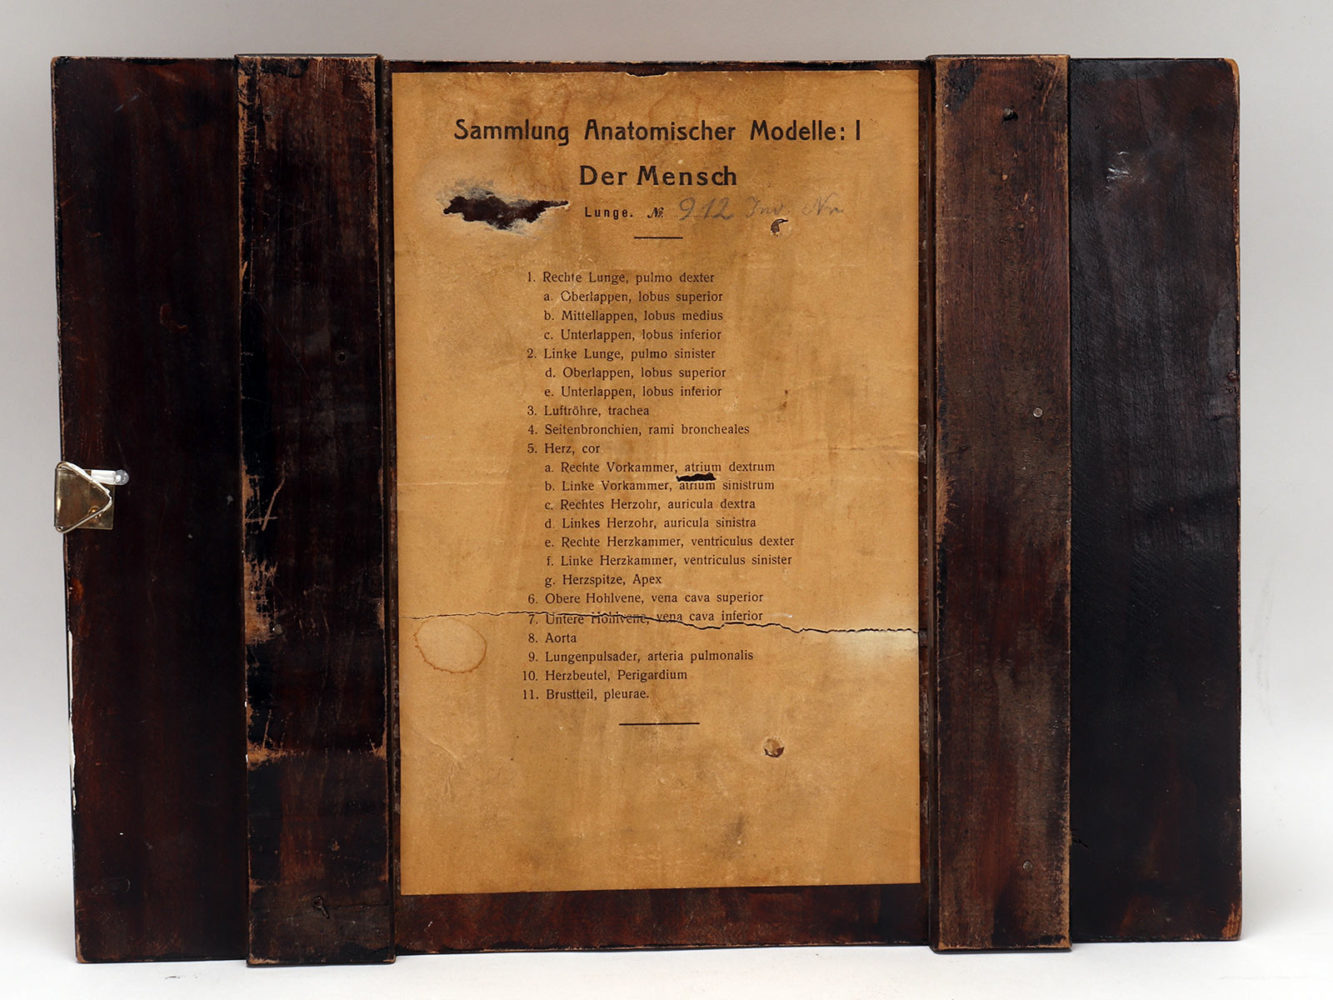

Rare anatomical model for class, depicting human lungs and heart, made out of painted plaster, mounted on a black fruit wooden base. By Louis M. Meusel, Germany circa 1920.